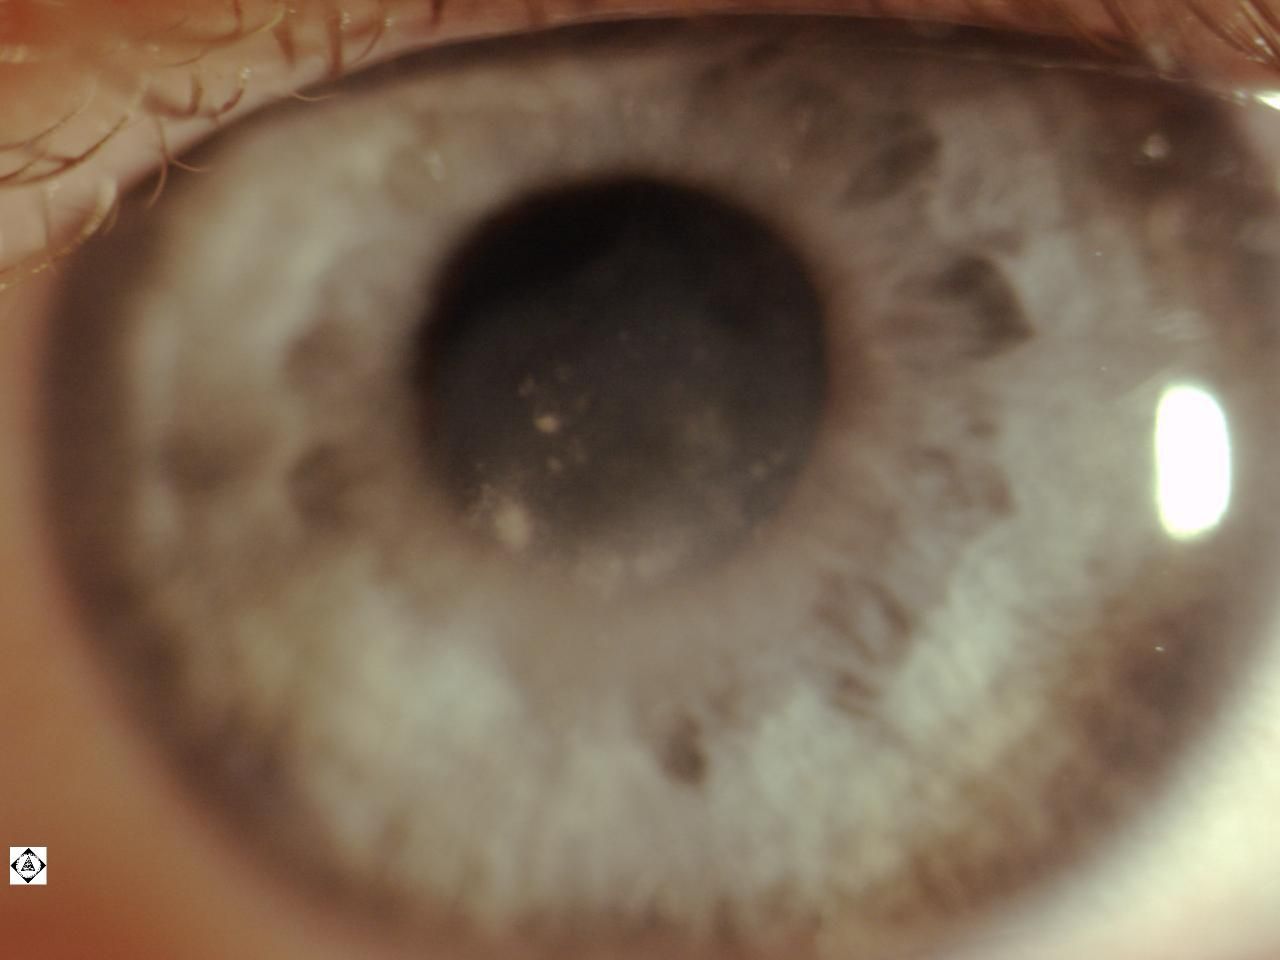

From sonorandeserteye.blogspot.com

Sonoran Desert Eye Center CORNEA SCAR Scar Treatment Center Palm Desert scar repair, or scar revision, is a procedure to reduce visible scars that remain after a wound has healed. remove unwanted scars and tattoos we also provide wide verity of services, wrinkle removal, permanent makeup, facial rejuvinetion, micro pen needling, coolsculpting fat freezing, lipo freeze,. self harm scar revision palm desert | palm spring | beauty rps.. Scar Treatment Center Palm Desert.